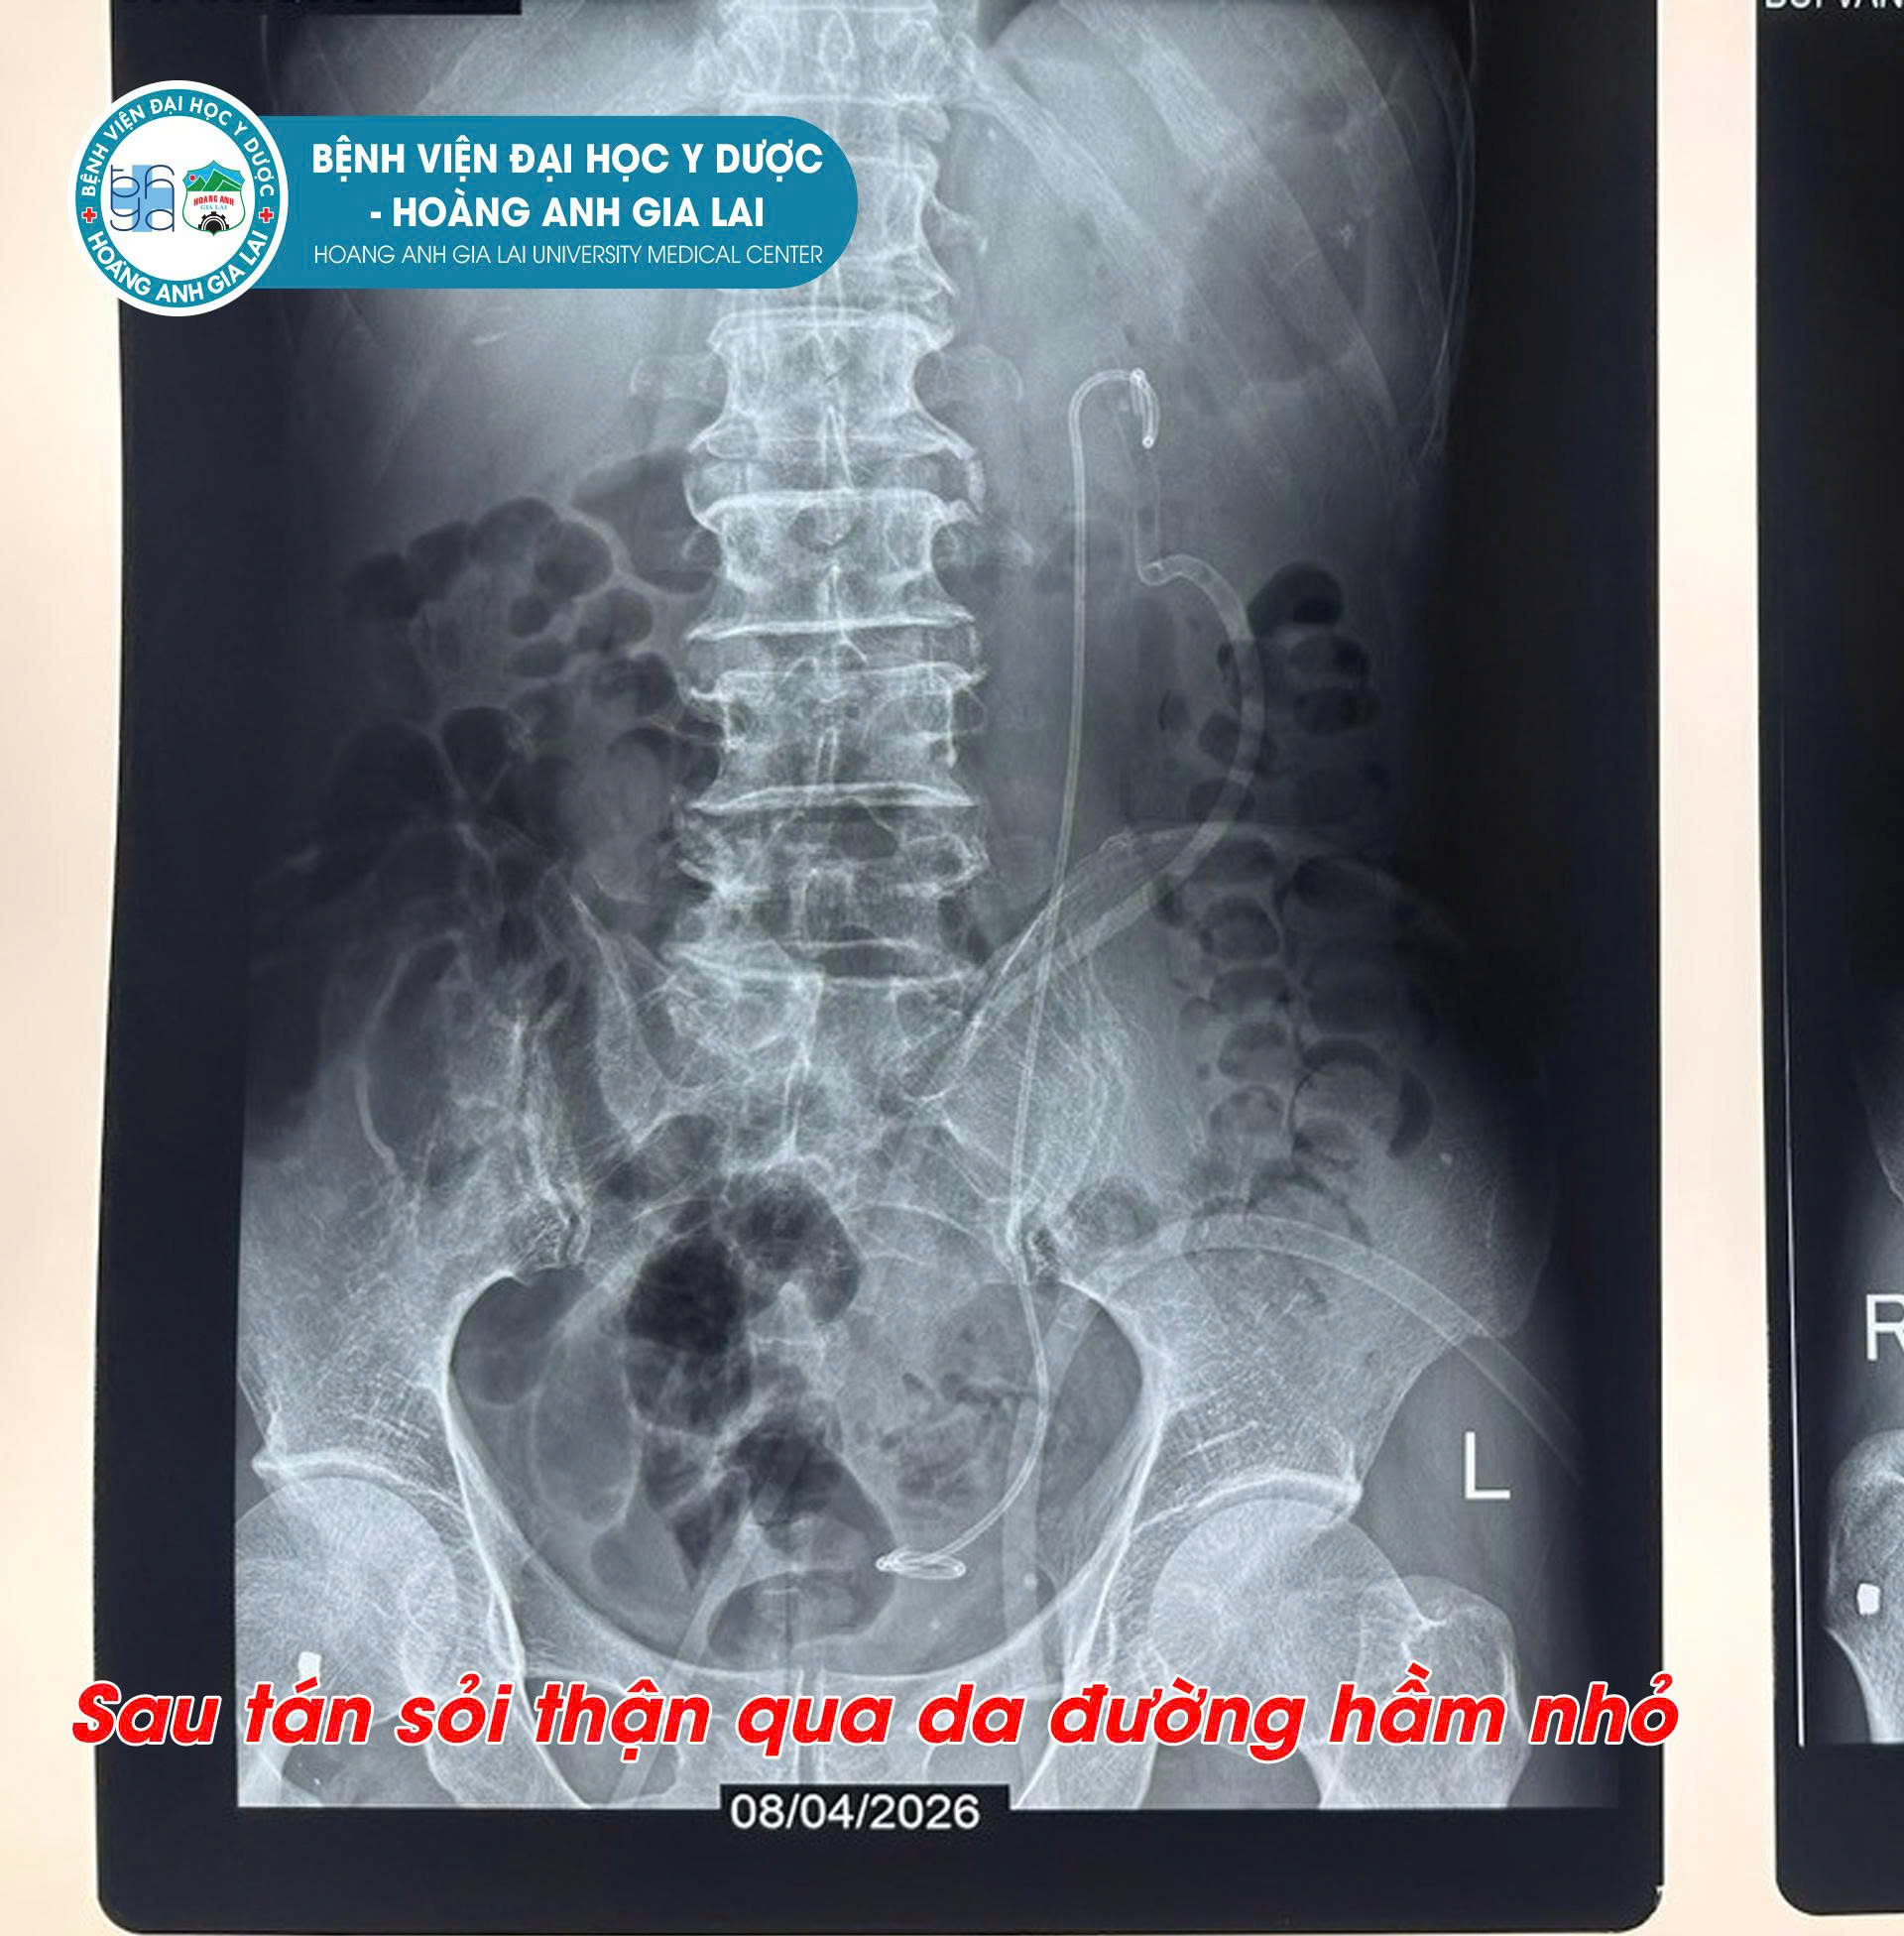

Trong số đó, kỹ thuật tán sỏi thận qua da đường hầm nhỏ (Mini PCNL) được xem là giải pháp tối ưu đối với những trường hợp sỏi kích thước lớn hoặc có cấu trúc phức tạp. Bằng cách tạo một đường hầm nhỏ tiếp cận trực tiếp vào thận, bác sĩ có thể tán và lấy sỏi ra ngoài một cách chính xác, giúp giảm đau, hạn chế mất máu và rút ngắn đáng kể thời gian hồi phục.

Ngày 11/4 vừa qua, Bệnh viện Đại học Y Dược – Hoàng Anh Gia Lai đã ghi nhận dấu mốc chuyên môn đáng chú ý khi thực hiện thành công liên tiếp 3 ca Mini PCNL cho các bệnh nhân ở nhiều độ tuổi khác nhau. Các ca can thiệp đều diễn ra an toàn, đúng quy trình, xử lý triệt để sỏi và mang lại kết quả điều trị tích cực.

Sau phẫu thuật, sức khỏe của cả 3 bệnh nhân đều ổn định, phục hồi tốt và đang được theo dõi hậu phẫu theo đúng phác đồ chuyên môn.